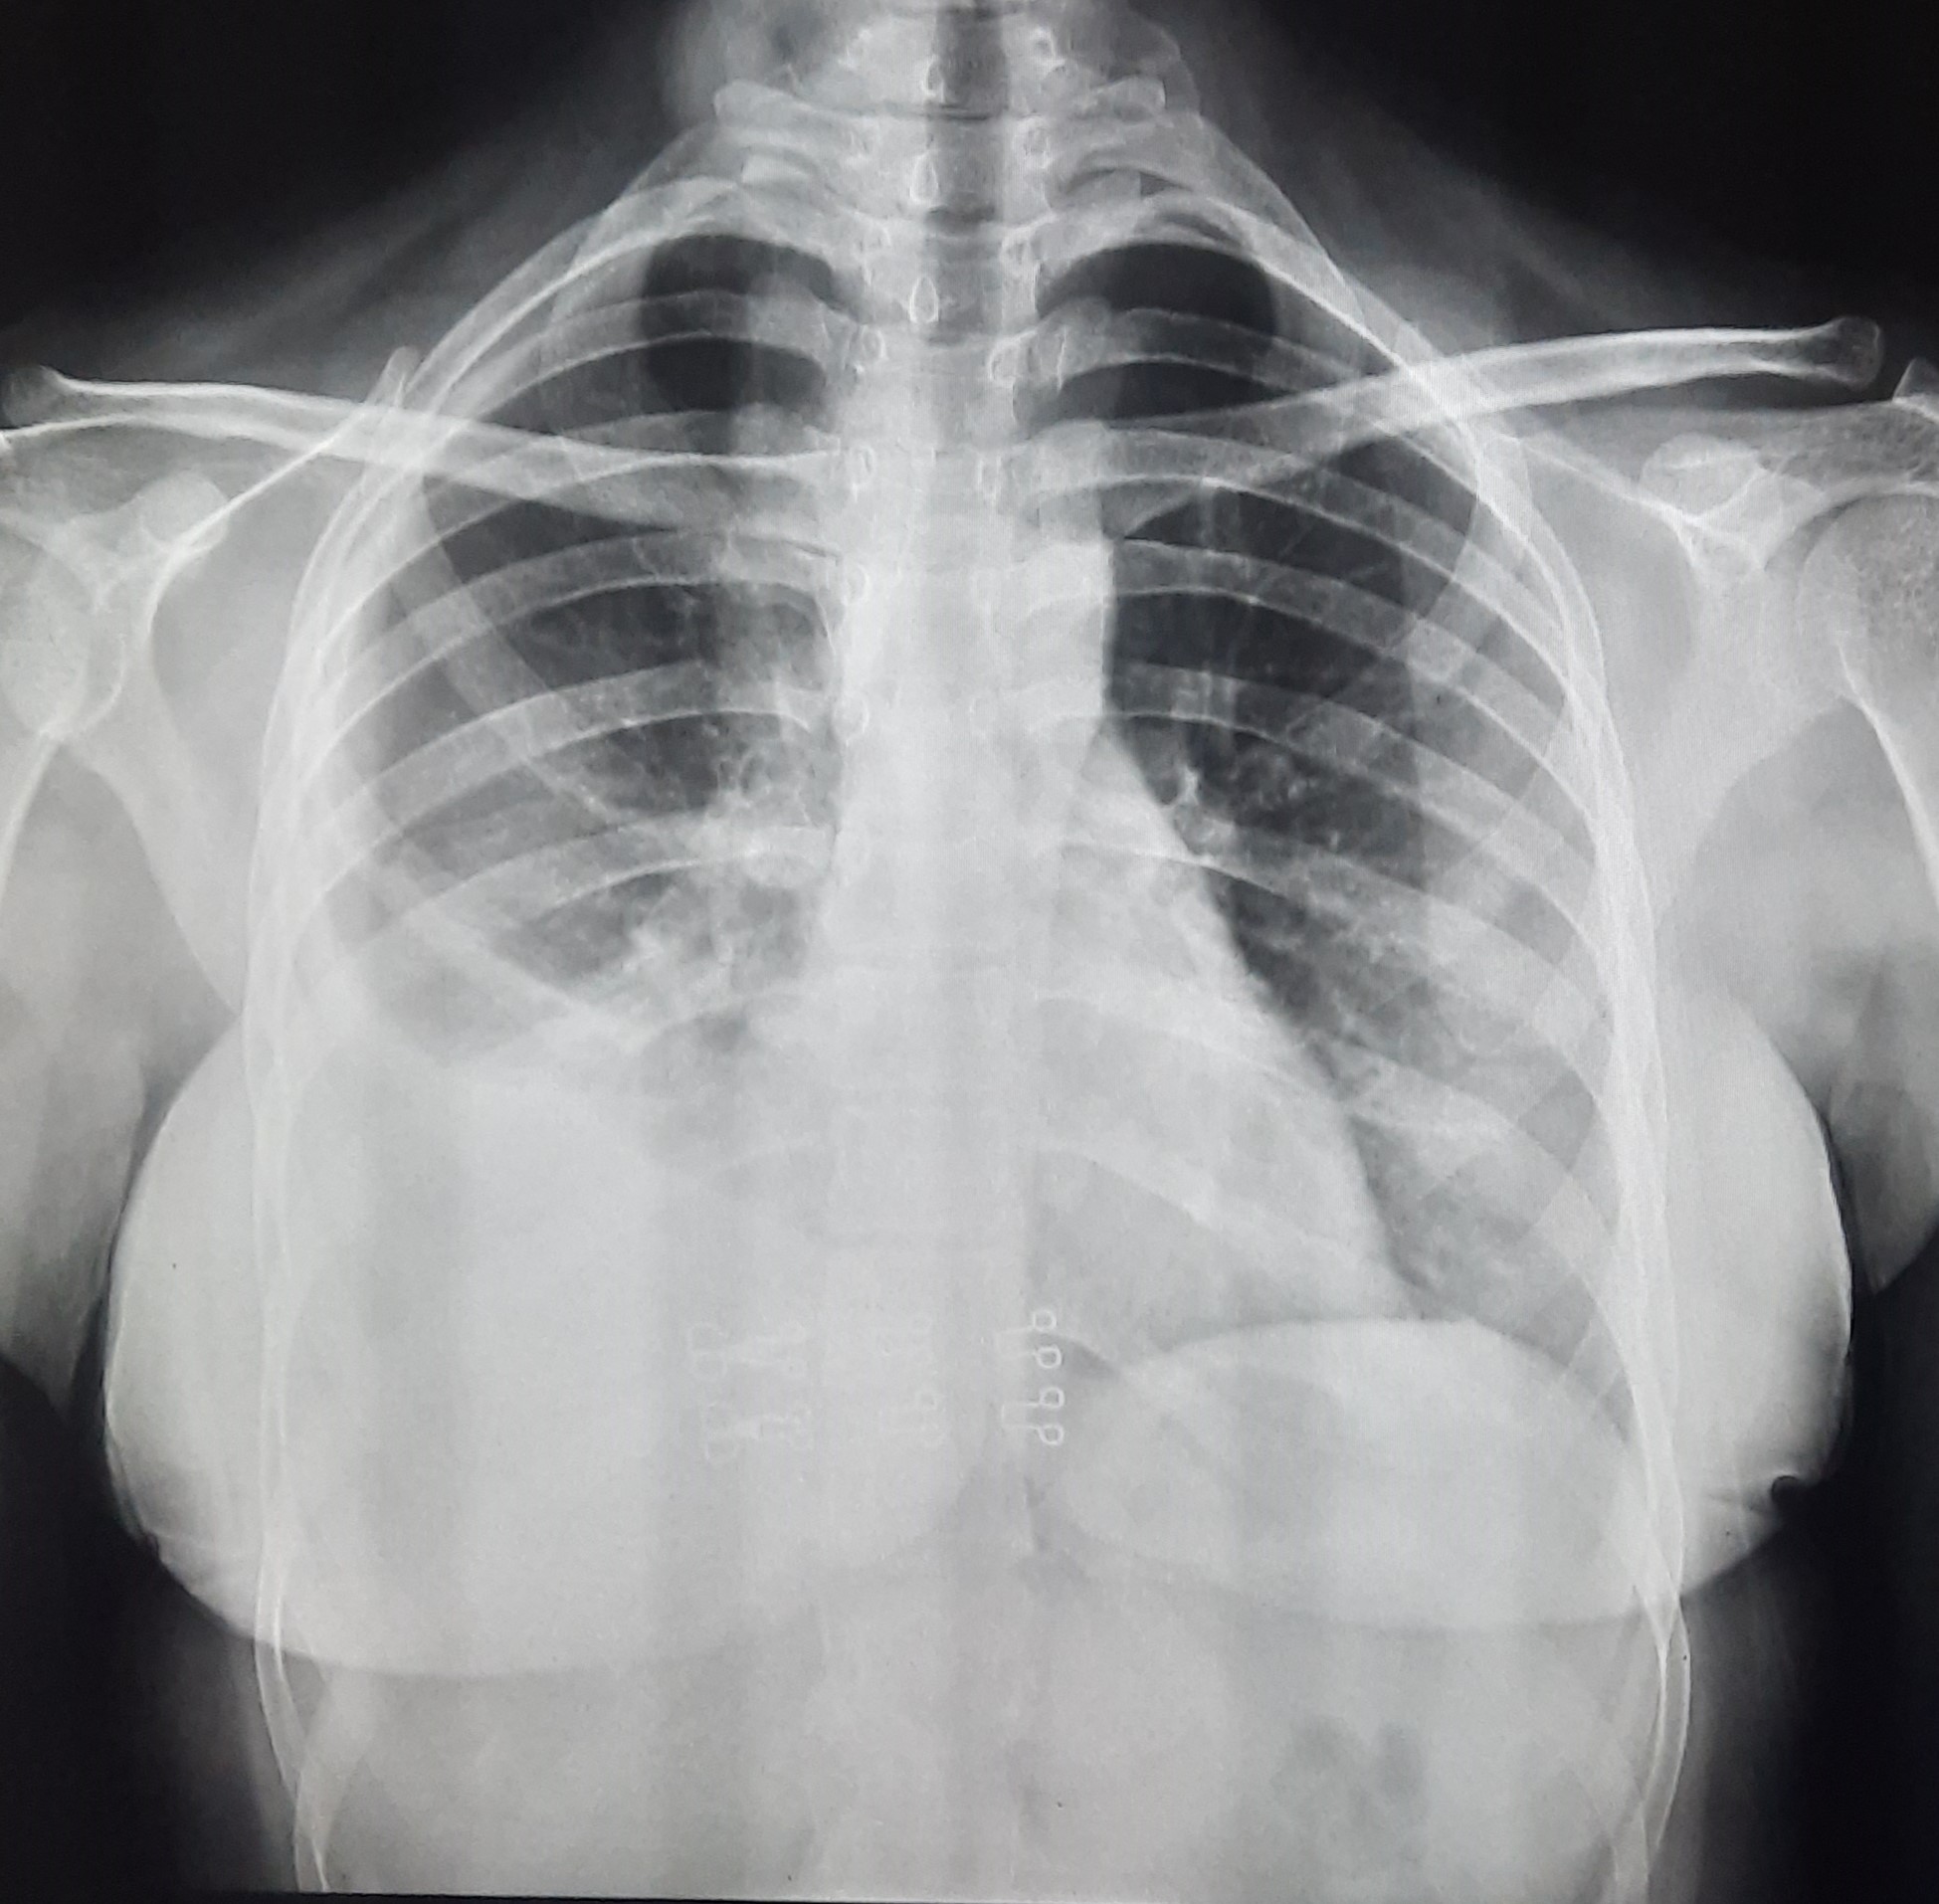

| 78 | IGGMC, Nagpur, Nagpur | P2 | 29-4394 | Priyanshi Suttamvar | Consent taken on Paper | 20 Yrs. |

Provisional Diag : ?

Final Diag : ? |

Result awaited (Suspected TB/Non-TB) | bilateral Lower Zone Haziness? Breast shadow, right sided Rib Crowding Present, Left Sided compensatory | Abnormality visible on x-ray |